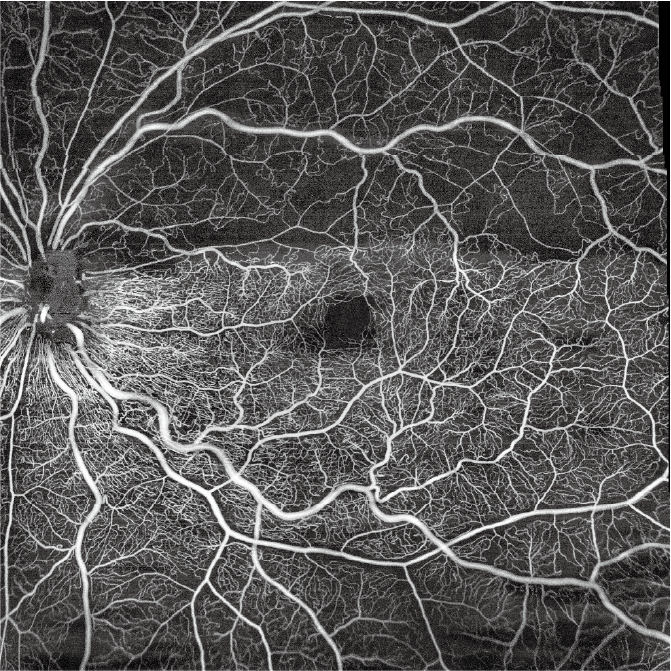

Full Range OCT-A

- 3 x 3 mm, 6 x 6 mm, 12 x 12 mm, 15×15 mm in één opname

- 20 x 20 mm met montage

- Automatische segmentatie in 7 lagen

- 6×6 mm papilscan met OCTA voor bloedstroomanalyse en dichtheidsmeting van bloedvaten in de macula